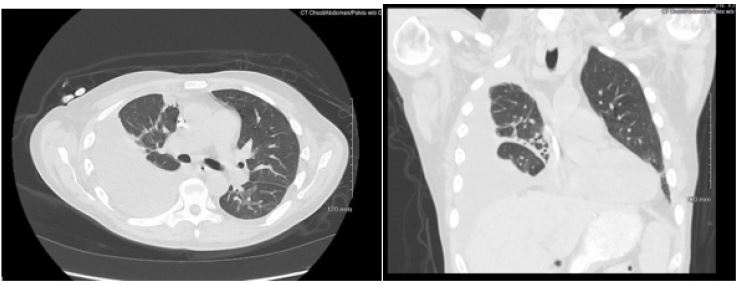

Patient presented with elevated blood pressure at 174/88. BMP was significant for Na 133, K 4.6, BUN 29, Cr 5.3. CMP is significant for Albumin 2.5. CBC was significant for Hb 8.7, Hct 25.0. D-dimer was found elevated at 4,670. PT and INR were normal. ABG significant for pH 7.52, pCO2 31.4, HCO3 25.3. A chest x-ray on admission demonstrated a large right-sided pleural effusion, contributing to significant compressive atelectasis of the right lung and leftward deviation of the mediastinal structures. Thoracentesis was performed, which demonstrated blood- tinged serosanguinous fluid. Transthoracic echocardiogram demonstrated EF 60-65%, LV diastolic dysfunction, with trace mitral and tricuspid regurgitation, and was negative for pericardial effusion. CT Chest demonstrated a large volume right-sided pleural effusion without pneumothorax, with extensive progressive atelectasis throughout the right lung. There was also a trace left-sided pleural effusion and pleural thickening with round atelectasis in the posterior left lower lobe, as well as minimal interstitial edema in the left lung. A chest tube was placed with consistent drainage throughout admission. Repeat chest x-rays continued to demonstrate pleural effusion. Thoracotomy, decortication, and pleurodesis were performed with Video-Assisted Thoracoscopic Surgery (VATS), with significant improvement of symptoms. The pleural fluid biopsy was negative for malignancy and revealed fibrocollagenous tissue with chronic inflammation and a few reactive epithelial cells. Thorough review of the patient’s medication list led to suspicion that the patient’s 50 mg Hydralazine three times a day may be the offending agent. Anti-histone antibody titers were found to be elevated at 3.7. Free Kappa and Lambda light chains were elevated. Antinuclear Antibody (ANA) titers were found to be negative. Hydralazine was discontinued, and after chest tube removal and improved chest x-ray, the patient was discharged home. It was recommended that the patient follow up with their primary care provider and rheumatologist.

Figure 2: Axial and coronal view of chest CT with IV contrast demonstrating large right sided pleural effusion with compressive atelectasis.